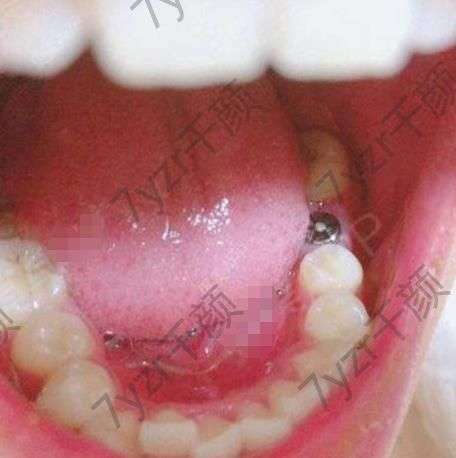

去醫(yī)院面診完已經(jīng)有半個(gè)月的時(shí)間了。因?yàn)樽约汗ぷ魈貏e忙,一直沒(méi)有時(shí)間去做手術(shù)。所以又拖了這么長(zhǎng)時(shí)間。今天終于把我的牙給種上了,醫(yī)院的護(hù)士都特別的溫柔。醫(yī)院的環(huán)境也特別的好。進(jìn)入手術(shù)室時(shí),醫(yī)生給我打上麻藥,之后很快就進(jìn)入了手術(shù),手術(shù)全程大概用了四十多分鐘的時(shí)間。手術(shù)過(guò)程中沒(méi)有太強(qiáng)烈的疼痛感。出了手術(shù)室又等了半個(gè)小時(shí),醫(yī)生觀察了一下我傷口的情況,確定沒(méi)有問(wèn)題之后告訴我可以回家了,七天之后再回醫(yī)院進(jìn)行拆線。

我的牙樁已經(jīng)種上三天的時(shí)間了,現(xiàn)在沒(méi)有特別強(qiáng)烈的疼痛感了,吃飯可以正常的吃了,只是不能用種牙的那一邊?,F(xiàn)在我還不能吃一些刺激性的東西,太辣,太涼,太熱,太硬的東西都不可以吃。昨天一個(gè)好兄弟,剛剛從外地過(guò)來(lái),還說(shuō)和我出去喝點(diǎn)酒。但是因?yàn)槲椰F(xiàn)在還在忌口,所以沒(méi)能去,因?yàn)槿チ酥蟊苊獠涣司褪呛染屏耍椅覀冊(cè)谝黄鹂隙ㄒ矔?huì)點(diǎn)一些。不應(yīng)該吃的東西。我還是自己在家再堅(jiān)持吃幾天清淡的飯菜吧。

已經(jīng)一周的時(shí)間了,現(xiàn)在也沒(méi)有什么特別的感覺(jué)了,今天早起就接到了醫(yī)院的電話,提醒我回醫(yī)院進(jìn)行拆線。到了醫(yī)院之后醫(yī)生已經(jīng)在等待著我了醫(yī)生檢查了一下我種植的牙樁說(shuō)恢復(fù)的很好。然后醫(yī)生就給我安排了拆線。醫(yī)生說(shuō),種完牙樁之后還要等一個(gè)多月才能把那顆牙種上。之前因?yàn)檫@個(gè)牙窟窿吃東西的時(shí)候特別難受,馬上我的這顆牙就要種好了。想想一下,以后吃東西都不礙事了。

現(xiàn)在我的牙已經(jīng)沒(méi)有什么特別的感覺(jué)了,傷口恢復(fù)的也很好。醫(yī)生說(shuō)只能等我的牙齦的骨頭和種植體長(zhǎng)到穩(wěn)定的狀態(tài)之后,才能裝上牙冠。我現(xiàn)在時(shí)不時(shí)的就會(huì)用我的舌頭去碰一下牙樁。感覺(jué)還有些不適應(yīng),不過(guò)我相信再等待一段時(shí)間肯定就會(huì)慢慢適應(yīng)的,我還尋問(wèn)醫(yī)生大概多久可以適應(yīng)下來(lái),醫(yī)生說(shuō)大概需要三個(gè)月的樣子,其實(shí)我感覺(jué)三個(gè)月說(shuō)長(zhǎng)也不長(zhǎng),說(shuō)短也不短,實(shí)在是太難熬了。

前幾天去醫(yī)院復(fù)查的時(shí)候,醫(yī)生說(shuō)在恢復(fù)一周的時(shí)間就可以給我裝上牙冠了,裝上牙冠之后如果不是特別硬的東西都可以吃了,實(shí)在是太開心了,種植完這一顆牙之后,我一定要好好得保護(hù)我的牙齒。